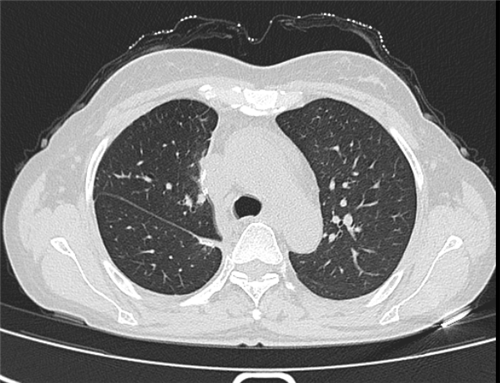

图1、2、3分别为抗真菌治疗前、治疗后和手术后的肺部CT检查影像。

让一家人没有想到的是,酒席结束后不久,顾女士出现了气促、胸闷、咳嗽、食欲下降、不能平躺的症状,甚至出现了濒死感。张丽华副主任医师立即为其安排了肺部CT检查,发现她的右上肺有一个8cm大小的肿物。为了明确诊断,顾女士接受了肺部纤支镜检查,检查结果让大家倒吸一口凉气,肺泡灌洗液检测结果显示,她的肺部多种细菌感染,其中最主要的为肺毛霉菌感染,而肺毛霉菌感染的死亡率极高。

所幸通过努力,顾女士肺部病灶缩小到2CM,迎来5月22日的手术机会。由胸外二病区主任周亚夫主刀,顾女士接受了右上肺叶切除术。肺毛霉菌感染导致肺易出血的倾向,反复炎症导致的肺门结构瘢痕化,肺动脉与支气管之间粘连严重,分离困难,手术团队巧妙地在腔镜下运用解剖剪做锐性分离,最终在3cm切口的单孔胸腔镜下顺利地切除病肺,术中失血小于100ml,术后顾女士第二日即下床活动,术后3日内顺利拔除胸腔引流管转回风湿免疫科。